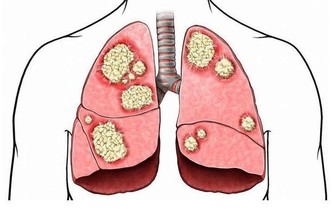

一旦反復出現這些症狀,不但會導致整體的免疫功能受到影響,還會影響到心臟的正常供血,患有心梗或者是冠心病等一系列心血管疾病的概率會比較高。所以在進入夏季時,一定要做好心臟的養護工作。那麼,在夏季時到底該如何養護心臟呢?

如果在夏季時出現了心悸、心慌、胸悶、胸痛、呼吸不暢、頭暈等現象,必須快速入院檢查並治療,才能最大程度維護心臟健康。